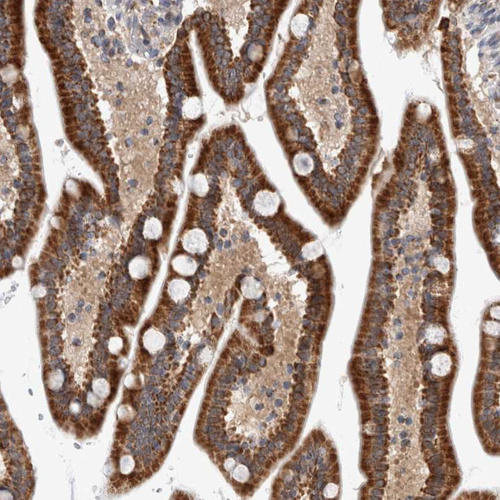

Immunohistochemical staining of human duodenum shows strong granular cytoplasmic positivity in glandular cells.